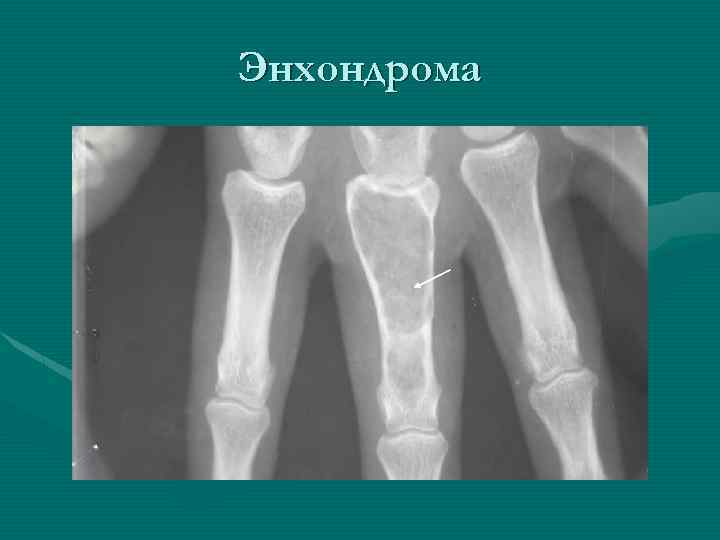

Хондромы - хрящевые опухоли, часто множественные, неправильно округлой или овальной формы, окруженные истонченным и оттесненным, но непрерывающимся корковым слоем. На фоне просветлений, обусловленных опухолью, определяются участки обызъвествленного хряща. В зависимости от характера роста их делят на экхондромы и на энхондромы. Экхондромы растут внаружу от кости, а энкондромы – внутрикостно.

Энхондрома